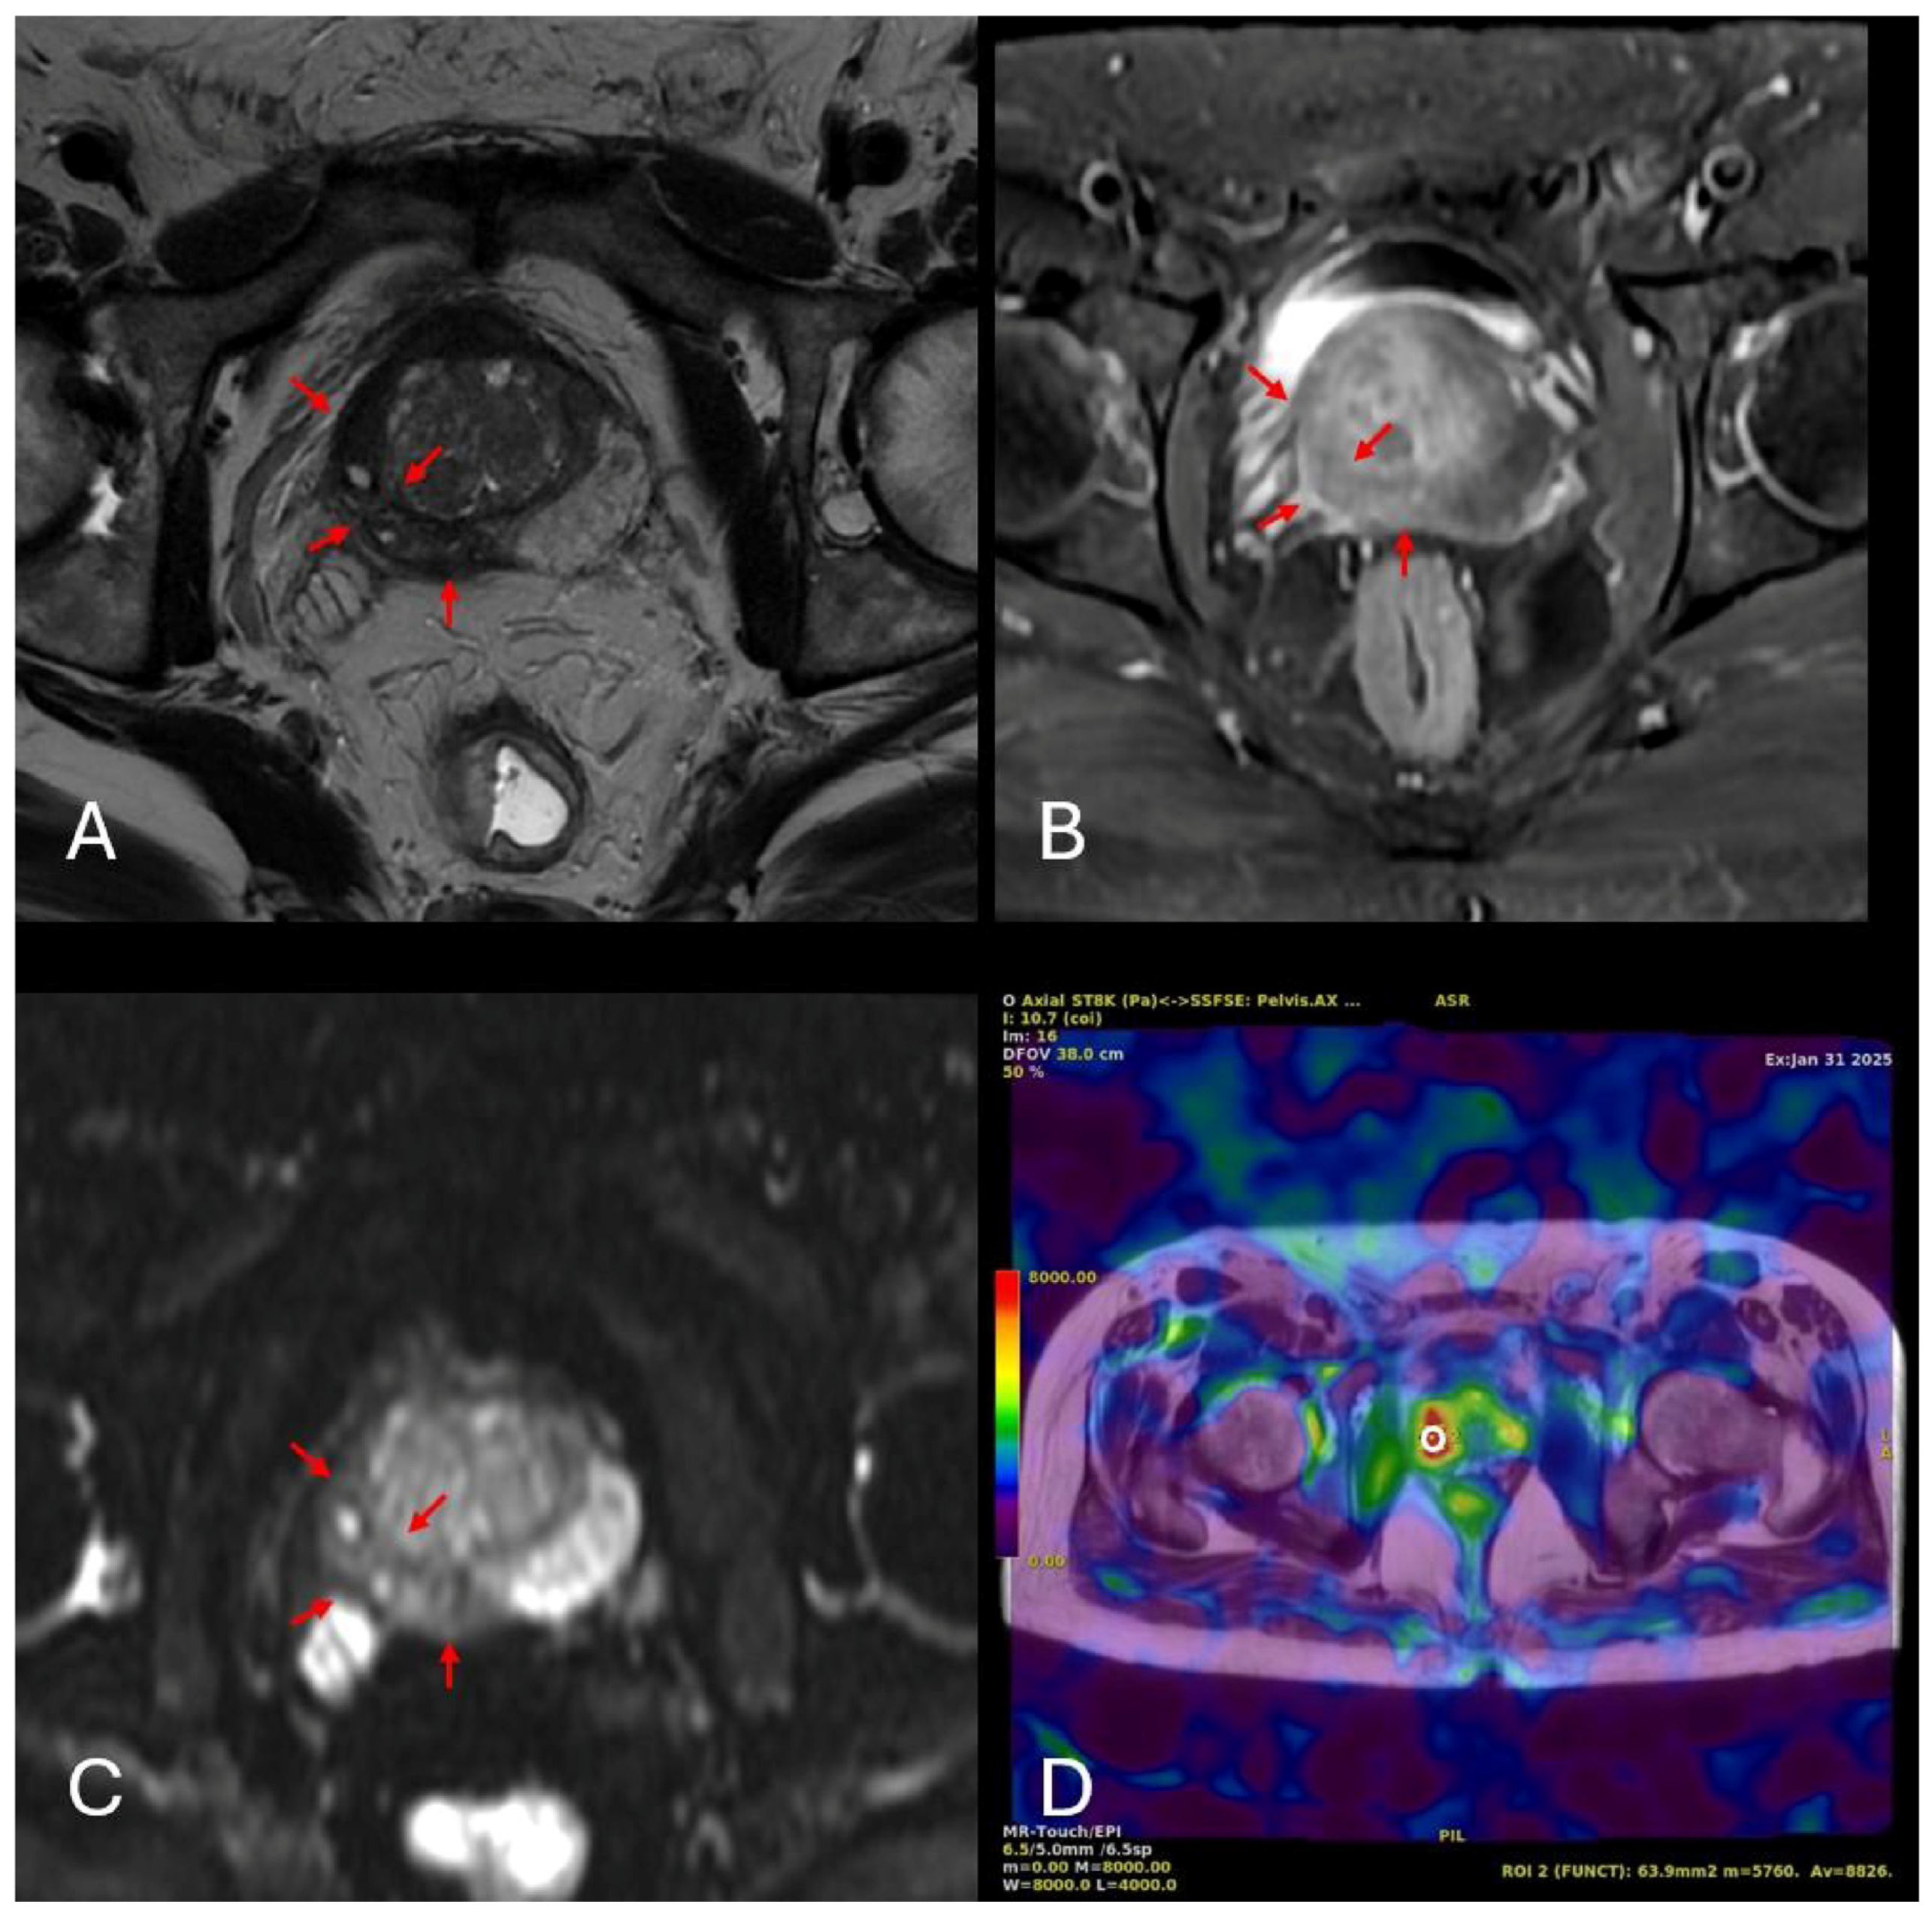

2.4. Radiological Measurements